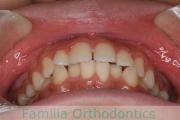

出っ歯を治したいということで小学生の時に来院されました。中学生になるまで経過観察をして、診断、上下左右から小臼歯を抜歯してマルチブラケット法にて治療を行いました。2年強、30回程度の通院が必要でした。

口元の突出感も大きく改善しています。

上下とも前歯の叢生(でこぼこ、凹凸、ガタガタ)がありましたので、保定をしっかりやらないと後戻りのリスクが出てきます。